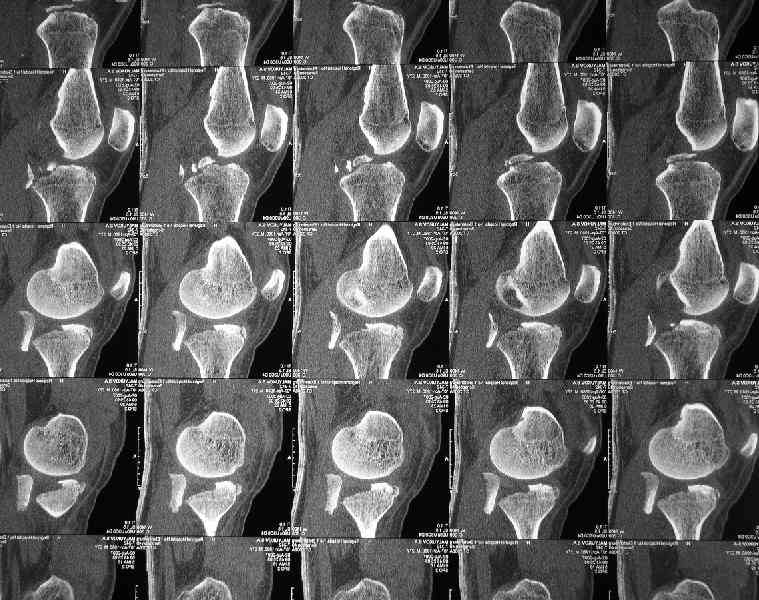

Молодой человек(27 лет) получил травму в ДТП 2 недели назад(23.07).Хотелось бы получить ответы на следующие вопросы:1.Какой доступ предпочесть?

2.Чем фиксировать? Заранее спасибо за конструктивные ответы.